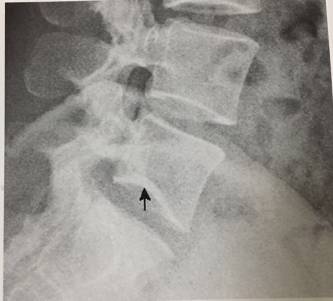

16、“丘比特弓”征

男,28岁。L5下终板向上突,呈“丘比特弓”样改变,为正常变异,需与许莫结节鉴别,后者范围小,呈局限性上突,且弧度不光整。